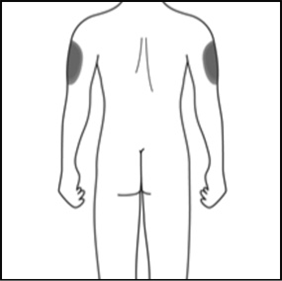

2a. Wählen Sie Ihre Injektionsstelle:

2b. Nur für Betreuungspersonen oder medizinisches Fachpersonal:

Falls eine Betreuungsperson oder eine medizinische Fachperson Ihnen die Injektion verabreicht, kann die Injektion auch an der Außenseite der Oberarme erfolgen.